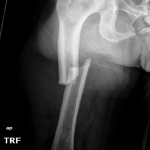

Meanwhile, Camilla, Duchess of Cornwall, tried to go down the rabbit hole but only her foot could enter. Rather than making it into the magical world of Wonderland, she ended up with a cast on her left leg.